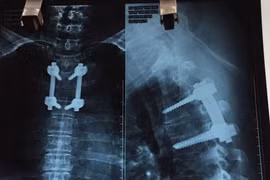

Một bệnh nhân nam 34 tuổi ở Nghệ An mang khối u “khủng“ nặng tới 45 kg đã được các bác sĩ Bệnh viện Việt Đức phẫu thuật cắt bỏ sau hàng chục năm gù lưng cõng khối u.